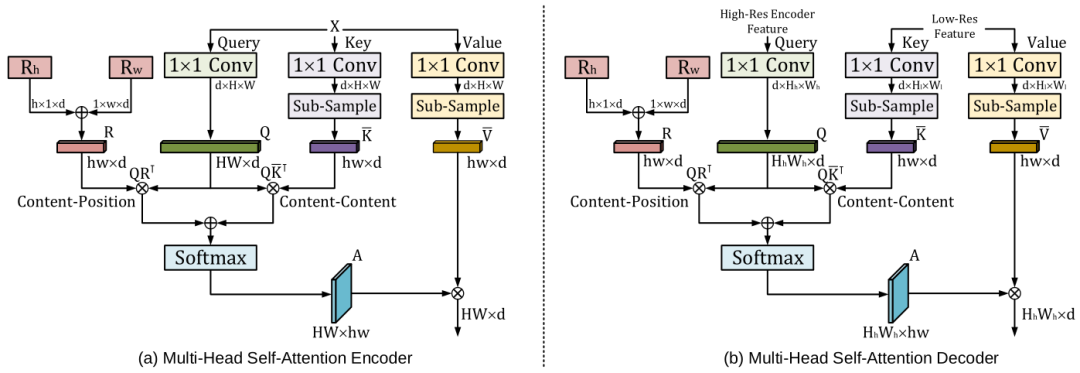

《UTNet: A Hybrid Transformer Architecture for Medical Image Segmentation》